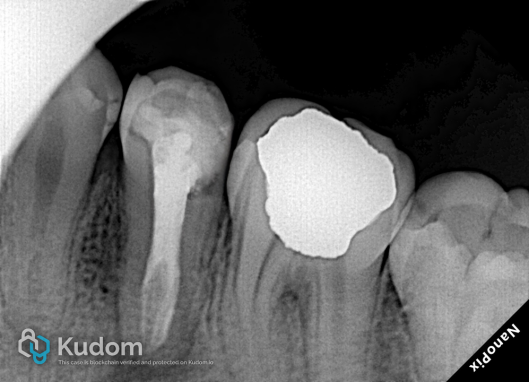

Treatment Outcome:Post-operative radiographs demonstrated excellent cleaning, shaping, and three-dimensional obturation of all four canals. The extreme anatomical curvature and the apical split were perfectly maintained without any shaping errors.

Clinical Significance:This case highlights the efficacy and reliability of modern microscopic endodontic techniques in managing complex retreatment cases. The exceptional flexibility and tracking ability of “the EZ Shaper Pro” system successfully addressed the extreme challenges posed by the 4-canal anatomy and apical split, establishing a solid foundation for long-term tooth preservation.